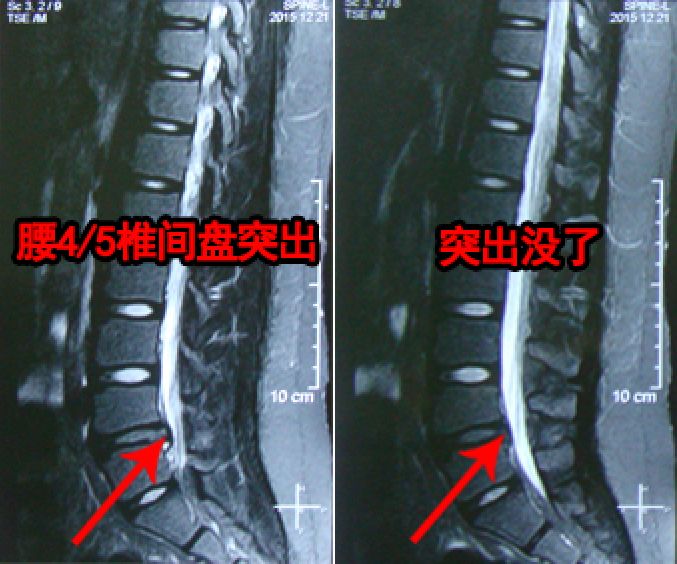

后来又上网买了5盒,贴完腰疼腿麻、坐骨神经痛全好了!不放心去医院查了下,腰椎间盘突出基本好了!我太感谢那个老中医了~